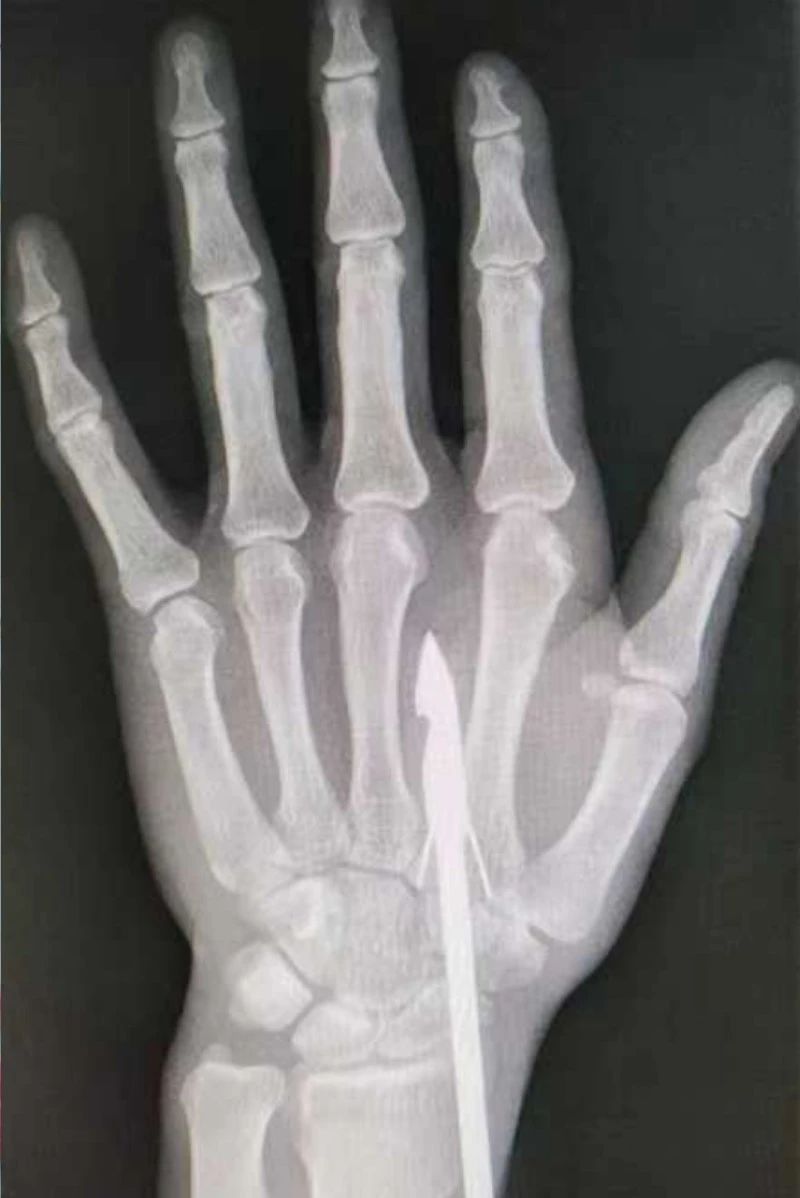

驚險,魚鉤“咬”到手!市骨科醫(yī)院手顯微外科巧解決

時間緊迫,每一秒的流逝都可能對傷者的手部功能造成不可逆的損害。接診醫(yī)生代彭威,迅速對傷者進行了初步檢查。他注意到,魚鉤已經(jīng)深深嵌入皮膚,情況遠比表面看起來復雜。沒有絲毫猶豫,立即安排了X線檢查以確認魚鉤的位置及傷及范圍,以及急診化驗檢查以評估患者的整體狀況。

確保在取出魚鉤的同時,不對周圍的組織造成額外的傷害。8點15分左右患者在局部浸潤麻下進行手術,經(jīng)探查后魚鉤未傷及重要血管、神經(jīng)及肌腱,經(jīng)過緊張的十分鐘,魚鉤終于被順利取出,隨后對傷口進行了仔細的清理和縫合,用敷料仔細包扎,確保傷口能夠順利愈合。